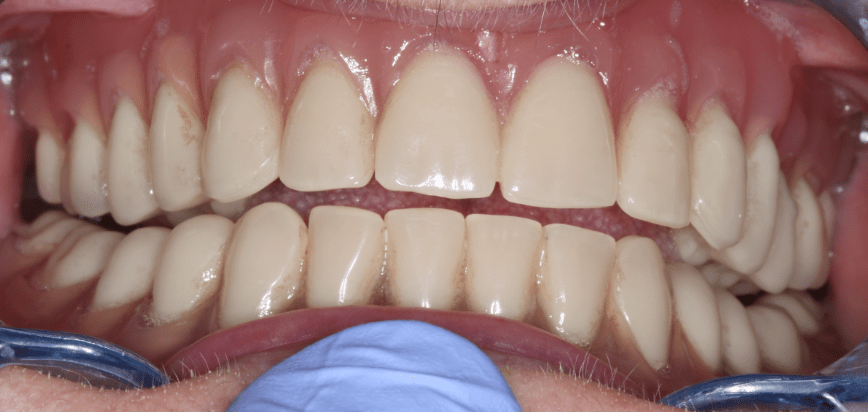

A fognyomatvétel után a laborban elkészített próbafogsorral ellenőriztük, hogy minden megfelelő a páciens számára, mind funkcionálisan, mind esztétikailag. A végleges műanyag (akrilát) fogak itt még viaszba vannak ágyazva: ezt a próbafogsort használjuk a próba során.

Fogpotlas teljes lemezes fogproba